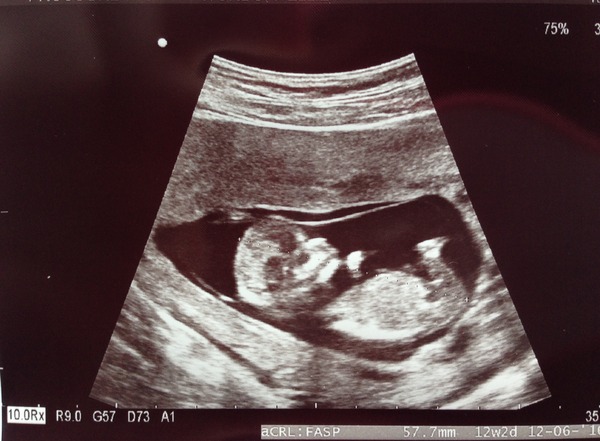

I should probably get through my 12 wk scan first before getting ahead of myself!! Roll on 11:30!